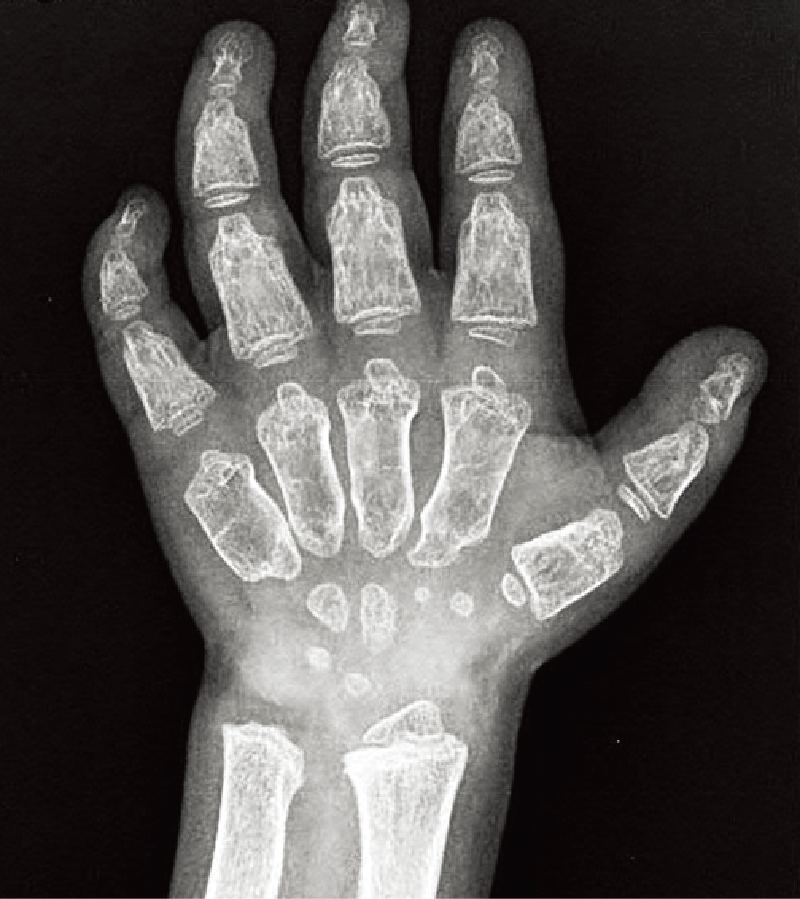

手指の短管骨は著しく短く、指節骨が弾丸状(bullet shaped)である。長管骨では骨端が小さく、骨幹端は幅が広い(B)。